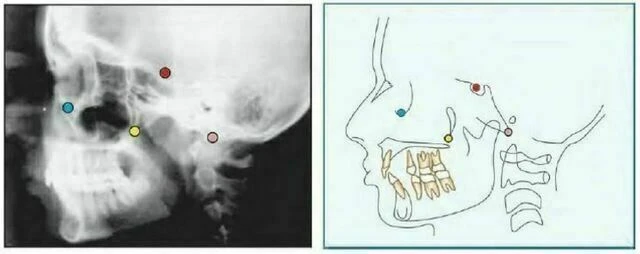

Orbitale (Or) là điểm nằm ở vị trí thấp nhất trên xương ổ mắt. Trên phim cephalogram theo chiều trước sau, mỗi điểm nằm riêng biệt nhau nhưng trên phim cephalogram mặt bên thì đường viền xương ổ mắt trùng nhau. Thông thường, điểm thấp nhất trên đường trung bình của xương ổ mắt được dùng để xác định mặt phẳng Frankfort.

Articulare (Ar) Giao điểm của mặt dưới nền sọ và mặt sau của cổ lồi cầu xương hàm dưới. Articulare được sử dụng một cách có hệ thống cùng với Condylion khi điểm này không nhìn thấy rõ. Sự thay đổi của vị trí lồi cầu sẽ làm điểm Artculare dịch chuyển.

Pterygomaxillary Fissure (Ptm) Có một hình ảnh có hình giọt nước, bóng phía trước là mặt sau của lồi cùng xương hàm trên. Điểm Ptm là giao của biên giới phía dưới của lỗ tròn với thành sau của khe chân bướm hàm.

Porion (Po) Đỉnh của ống tai ngoài. Đôi khi do khó xác định porion nên sử dụng đỉnh của bóng thanh tai, điểm này được gọi là “machine porion”